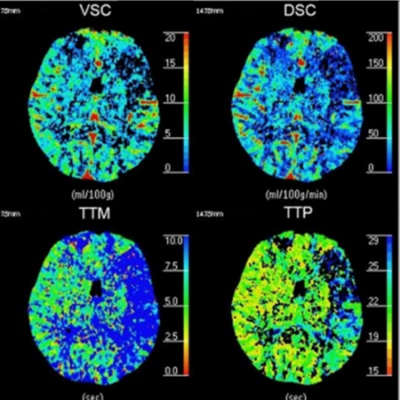

As concerns the Data Processing, this CT Brain Perfusion E-lerning ARRT CE credits course will cover the Cerebral Blood Volume, and Cerebral Blood Flow, as well as Mean Transit Time of the CT Brain Perfusion E-learning ARRT CE.

As well as the Time-to-Peak of the Tissue Response Function.